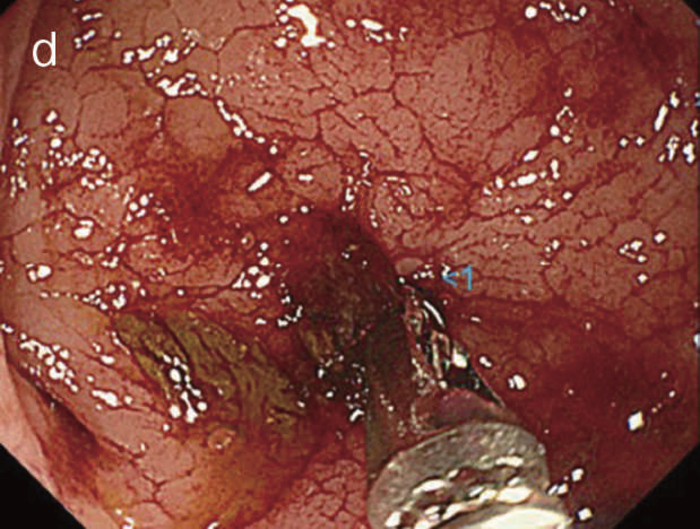

図26 痔瘻一次口から表出したクローン病関連腫瘍の直腸反転内視鏡観察像

粘液をともない,腫瘍性病変を強く疑う表面構造を有している。当初の生検病理診断は過形成性病変で,再検の後,直腸切断術を施行した。(文献1)から転載)